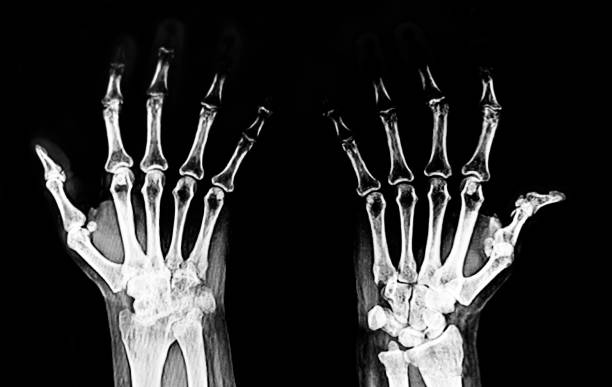

류마티스 관절염 초기증상 자세히 알아보기

류마티스 관절염은 활막이 존재하는 모든 관절에서 발생하는데 활막은 관절 주위를 둘러싸고 있는 조직으로 자가면역 기제에 이상이 생기면서 나타나는데 자가면역 이상은 외부 공격으로부터 신체를 보호하는 대신 공격하는 면역 체계의 이상으로 다양한 연령대에서 나타나고 있으며 우리나라 인구 1% 정도가 겪고 있는 것으로 알려져 있어 다른 질환과 마찬가지로 초기에 증상을 파악하고 대응하는 것이 좋습니다.

류마티스 관절염 초기증상 세 번째는 관절 통증입니다 류마티스 관절염으로 인한 관절통은 운동과 휴식과 무관하지만 손가락과 손목 통증은 류마티스 관절염에서 흔하게 나타나나 통증은 발목, 무릎, 엉덩이, 어깨, 팔꿈치와 같은 관절과 손목, 팔꿈치와 같은 좌우 관절에서도 발생합니다.

10. 류마티스 관절염 초기증상 - 뻣뻣한 손과 발

류마티스 관절염 초기증상 열 번째는 뻣뻣한 손과 발입니다. 류마티스 관절염의 초기 단계에서는 후관절에서 증상이 나타난다. 해당 증상은 손가락과 손이 만나는 관절이나 발가락과 발 사이의 관절에서 시작되며 시간이 지남에 따라 이 뻣뻣함이 다른 관절로 옮겨갈 수 있습니다. 증상은 아침이 아닌 하루 중 언제든지 나타날 수 있습니다.